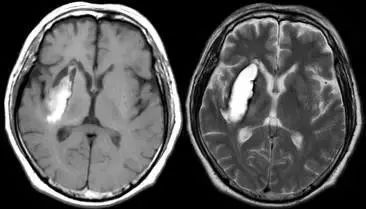

图片

脑出血慢性期

T1 低信号(左),T2 低信号(右)